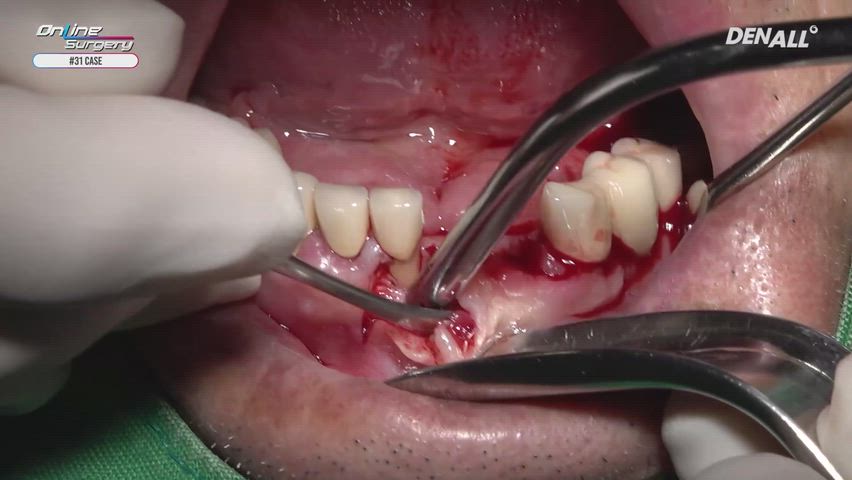

#15 Early implant placement with sinus lift with CAS KIT ...

Online Surgery

Views 545